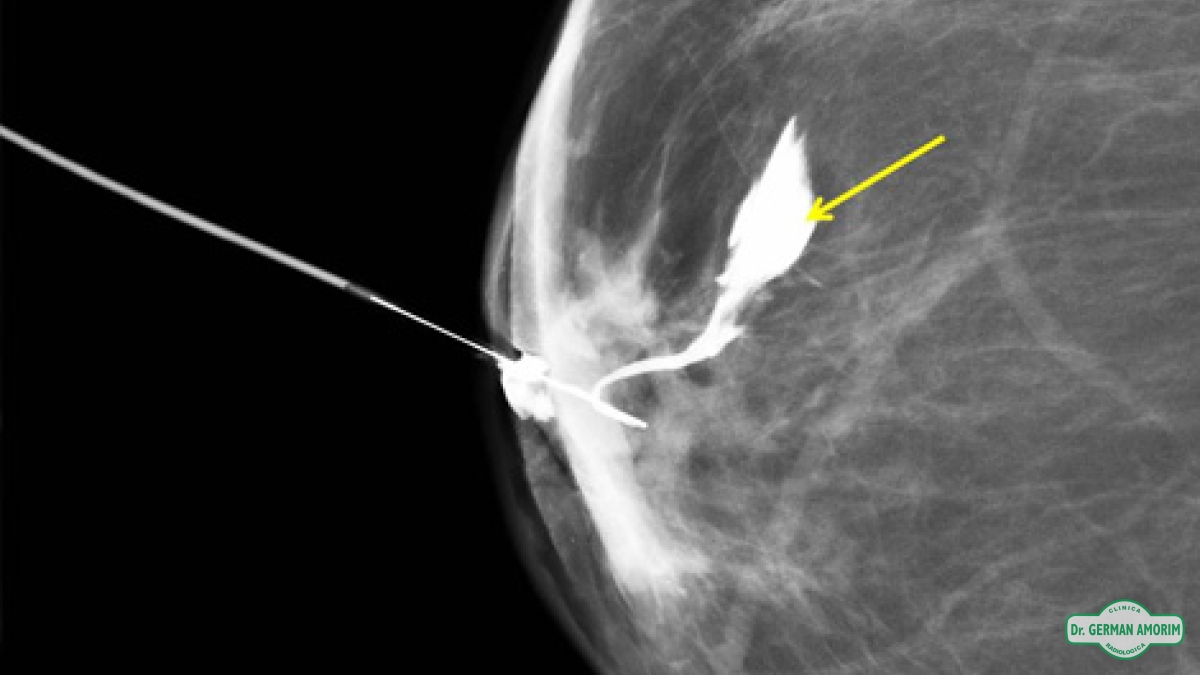

La lesión intraductal más frecuente es el papiloma y aunque el carcinoma intraductal tiene una frecuencia menor, al no poder distinguir entre ellas con este método de imagen, se recomienda la escisión quirúrgica. Es en este contexto que la galactografía sirve de mapa prequirúrgico para identificar correctamente el conducto patológico, la extensión de la lesión intraductal y la posible existencia de lesiones múltiples.

Entre las ventajas de esta técnica de imagen podemos mencionar la alta capacidad de definición de los ductos y de las posibles lesiones intraductales tras la administración de contraste, permitiendo así un mapa prequirúrgico para una escisión lo más selectiva posible.